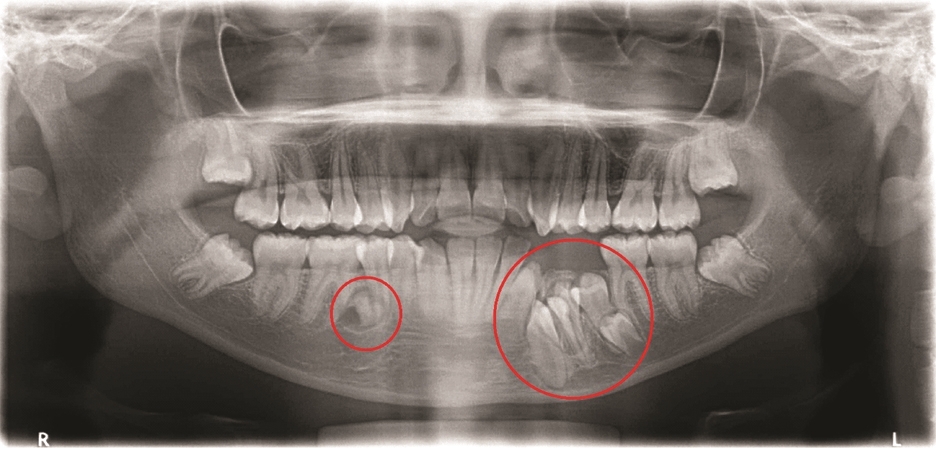

초진 엑스레이(2023.12.18)

오른쪽 아래 작은 어금니 부위에

매복 과잉치가 존재합니다.

(주로 파노라마에서 먼저 발견됩니다.)

특별한 증상은 없더라도

추후 낭종 발생, 인접치 치근 흡수 등

여러가지 위험 요소를 고려한다면

제거하는 것이 일반적입니다.